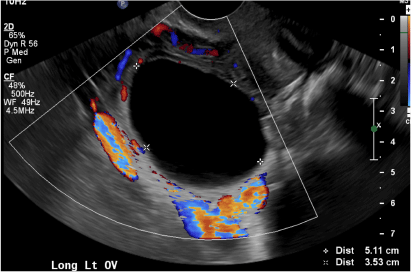

(E) Cystic ovarian neoplasm INCORRECT

These are large complex masses with both cystic and solid components demonstrating internal vascular flow. They usually demonstrate a thick irregular wall, multiple septations, and nodular papillary projections.3